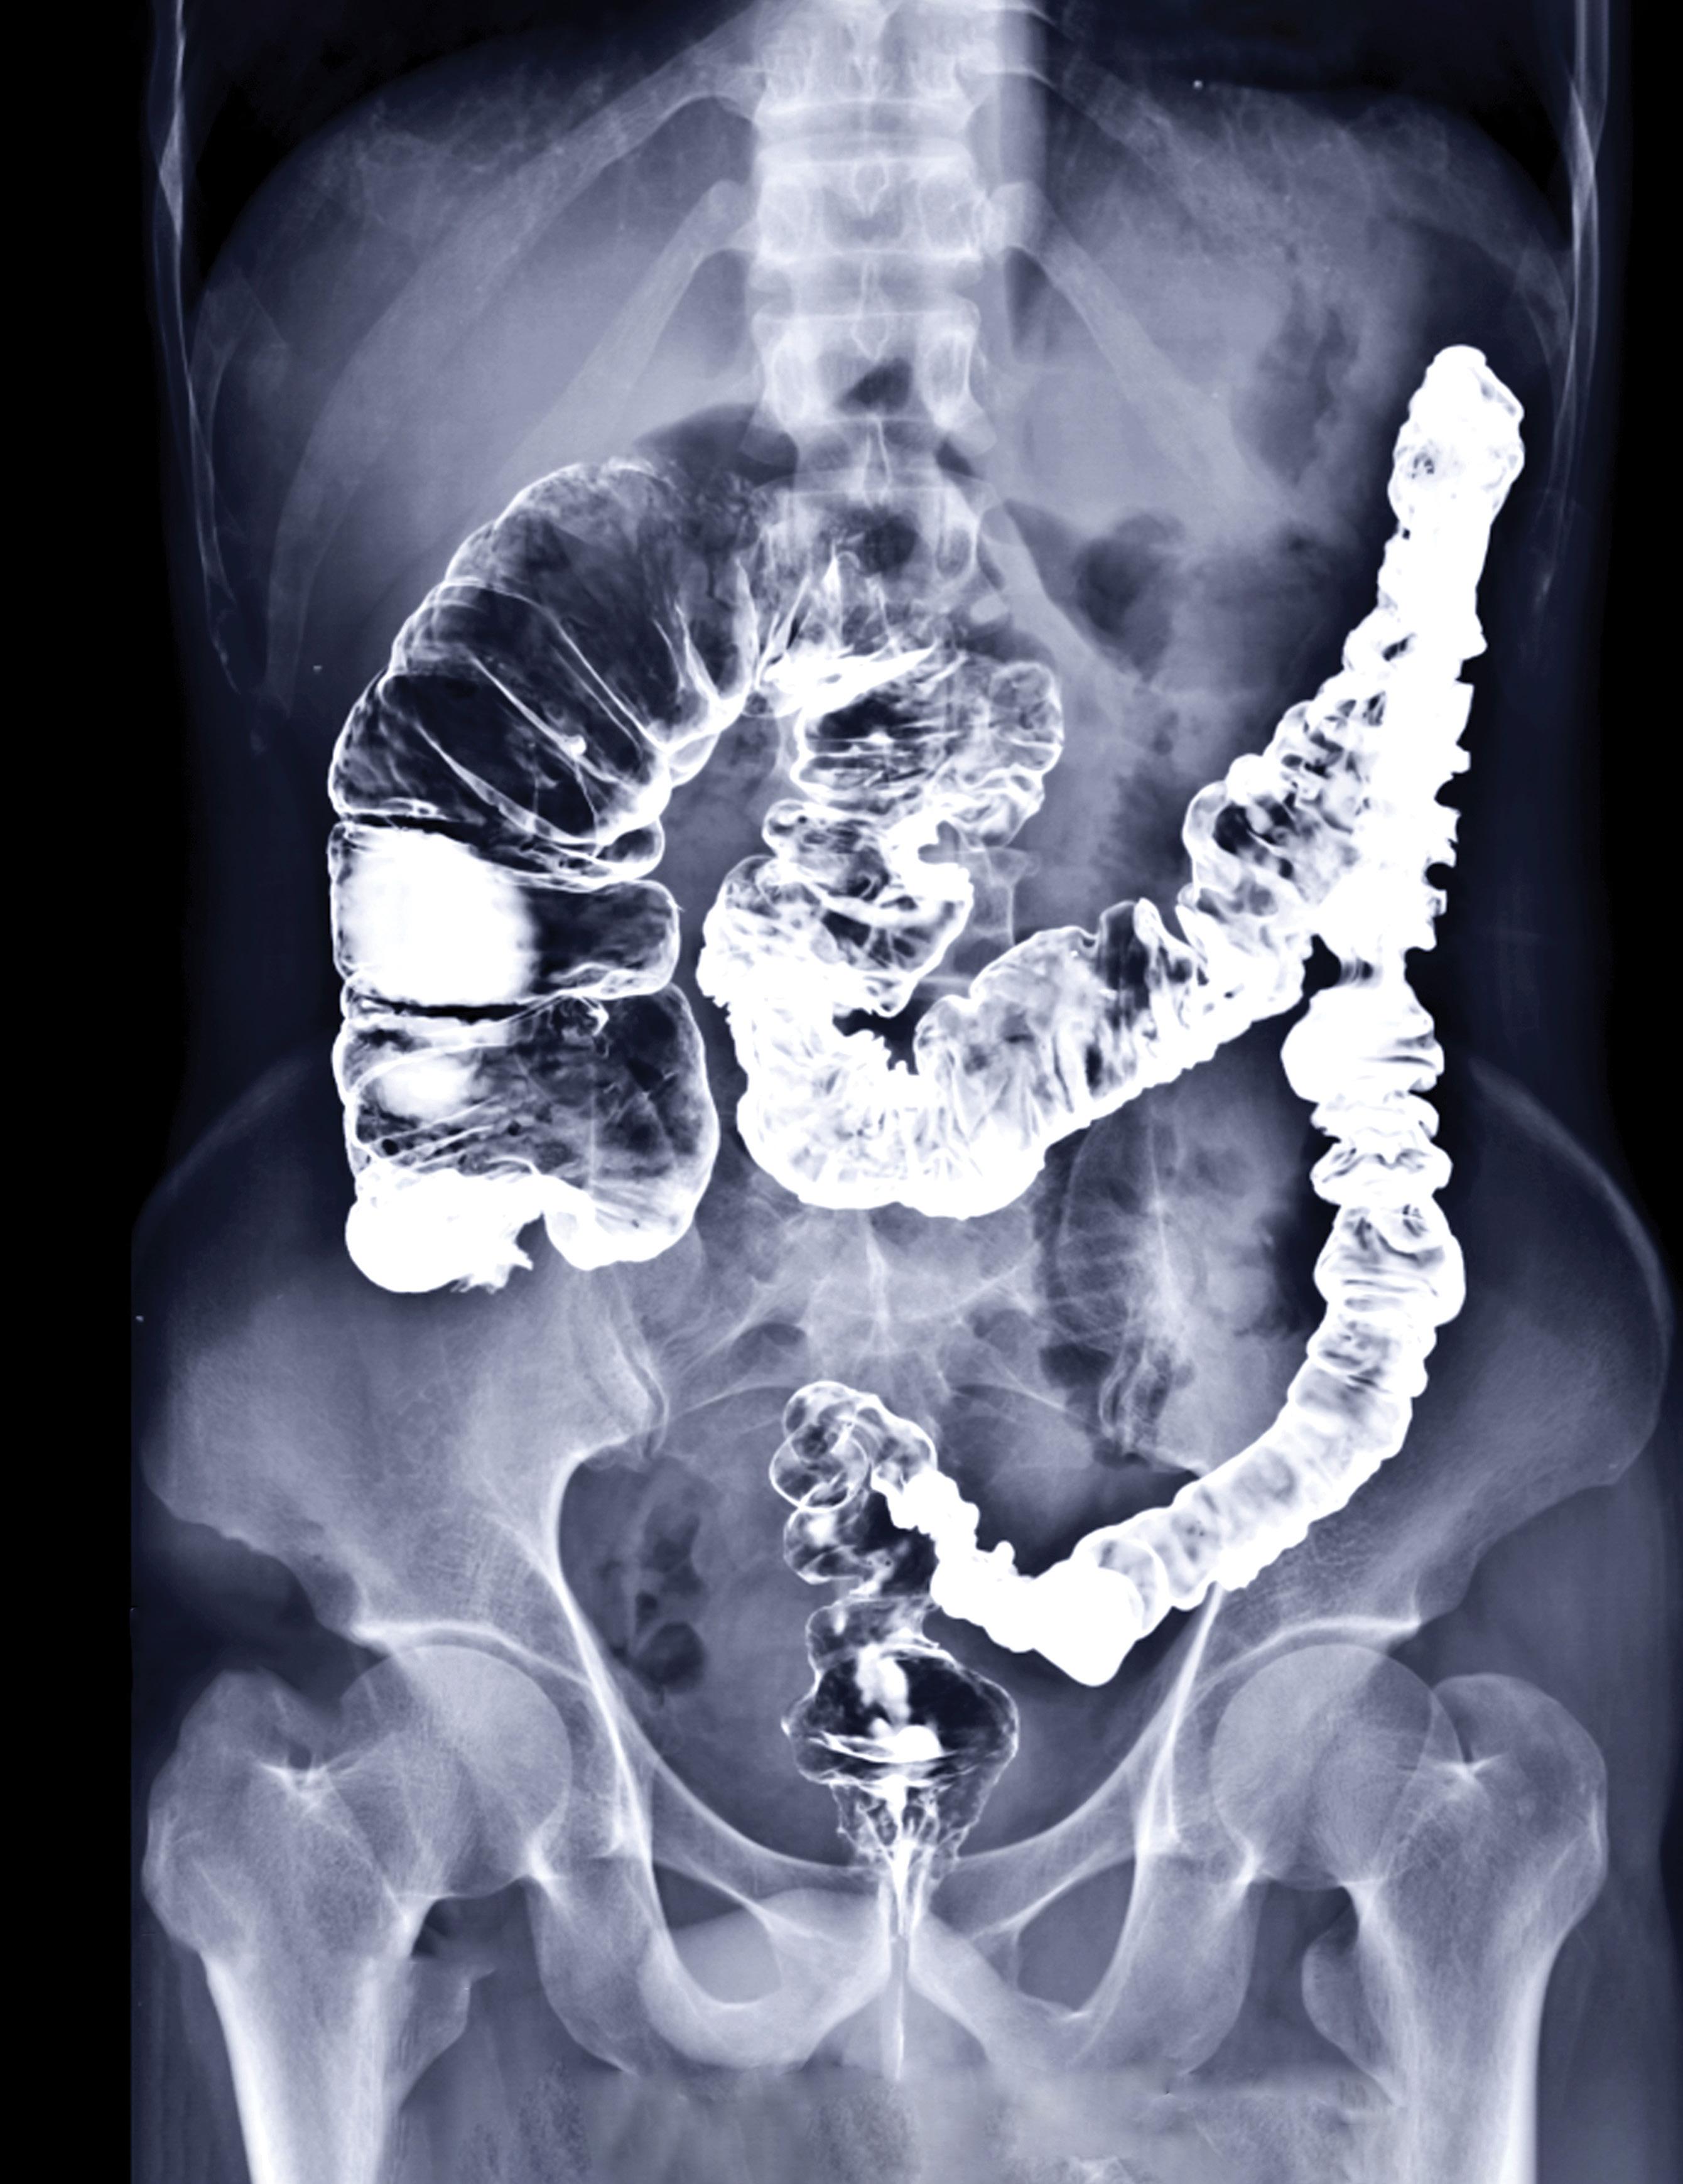

“The picture above is the large intestine (aka colon or bowel). It is highlighted in white from probably a barium x-ray procedure. In this x-ray you can see the beginning of the colon, the cecum and ascending colon are grossly expanded or herniated retaining fecal matter and sludge. This is happening because at the end of the bowel, (the descending and sigmoid colon) are so restricted that the fecal matter cannot get through and is literally backing up and expanding the previous parts of the colon. This leads to diverticulosis, diverticulitis, polyps, and eventually most likely colon-rectal cancer. Remember, according to medical texts, 100% of Americans will have some type of bowel disease by time they’re in their senior years.”